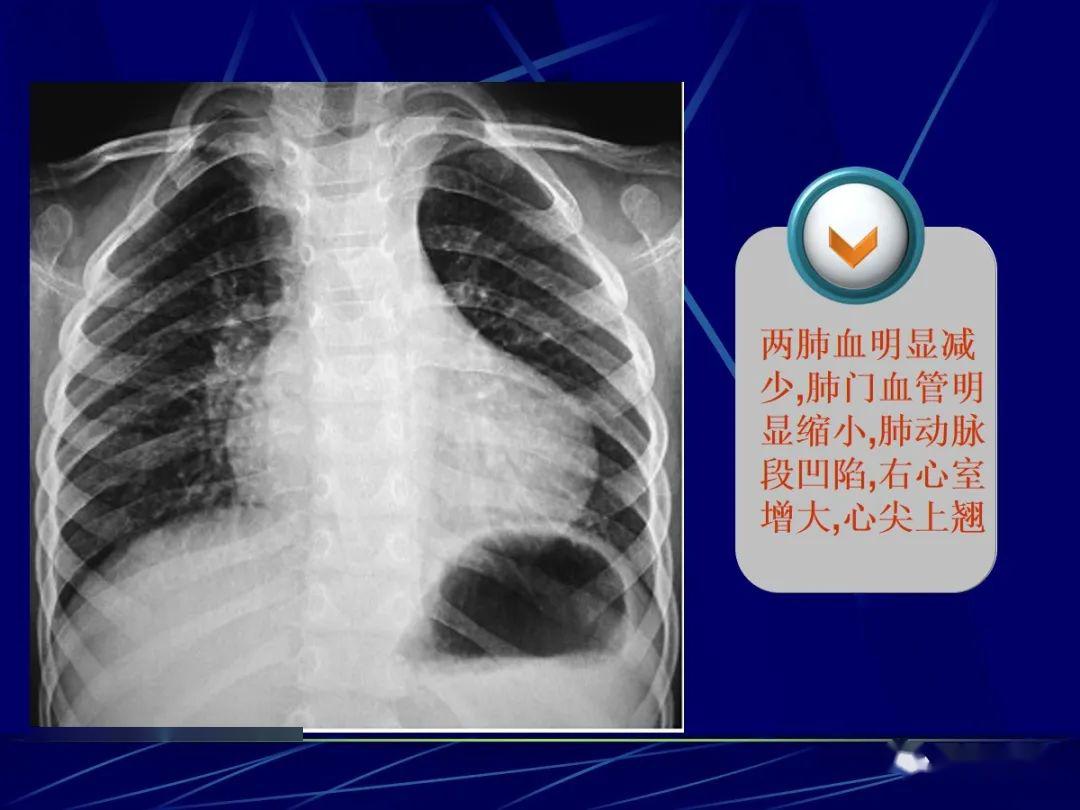

两肺纹理减少,透亮度增加,心尖圆钝上翘, 肺动脉段凹陷,主动脉影钥眄

右心室增大 后前位 (1)心腰平直或突起,心尖上翘 (2)相反搏动点下移

此后右心室流入道也肥厚增大,心尖上翘.有时还可见右心房扩大.